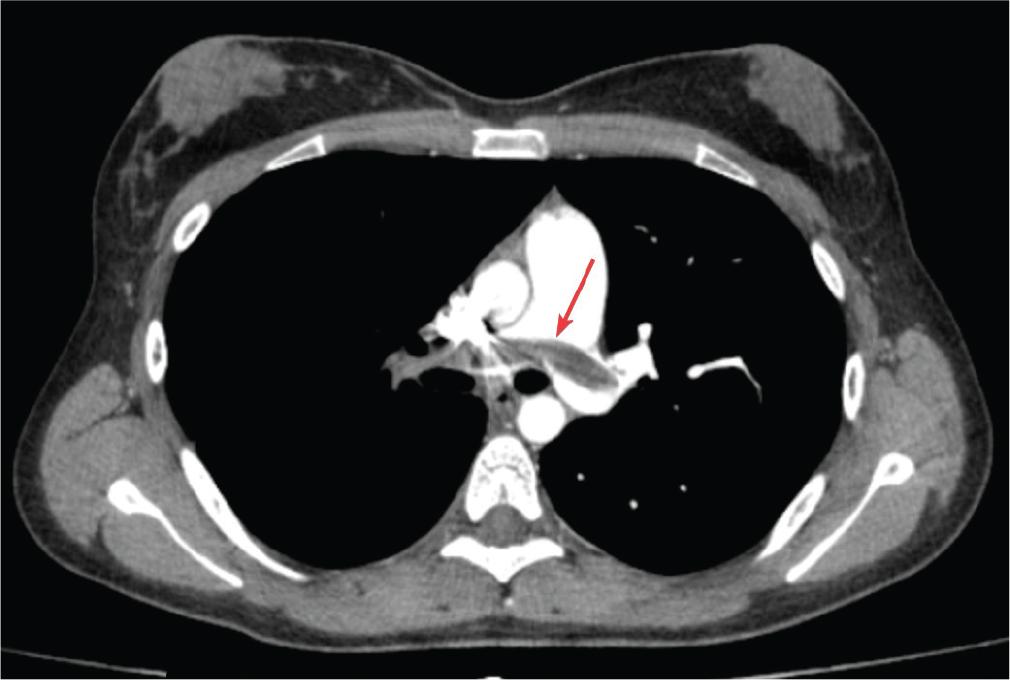

Patient A, a 22-year-old non-smoker with a 5-month history of COC use for dysmenorrhoea, presented with dyspnoea and palpitations with an acute onset 48 hr after physical exertion. The clinical examination revealed tachypnoea, peripheral oxygen saturation (SpO2) of 90%–91%, mild tachycardia (112 bpm) and arterial hypotension (90/60 mmHg). Given the clinical presentation and according to the revised Geneva score, the patient exhibited an intermediate clinical probability of PE (4). Blood tests indicated a low haemoglobin value of 9.9 g/dL, evidence of an inflammatory syndrome (C-reactive protein (CRP) = 58.11 mg/L) and elevated D-dimers (700 ng/mL). The electrocardiogram (ECG) revealed an incomplete right bundle branch block, and echocardiography showed moderate tricuspid regurgitation, moderate pulmonary hypertension (PH) with an estimated systolic pulmonary arterial pressure (sPAP) of 44 mmHg. Computed tomography (CT) confirmed the presence of a massive occlusive PE in the main pulmonary arteries and the ‘saddle’ of the pulmonary trunk, along with pulmonary infarctions in the lower lobes (Figures 1 and 2). Based on these findings and the clinical presentation, the patient was diagnosed with high-risk PE (4). Considering the haemodynamic status and the recent onset of symptoms (within 48 hr), the patient was admitted to the intensive care unit. She received systemic thrombolytic therapy (Alteplase), intravenous (IV) anticoagulation with an initial bolus of unfractionated heparin (UFH) 5000 IU followed by continuous infusion of 1200 IU/hr, as well as supplemental oxygen therapy. After 3 days, the patient’s condition significantly improved, allowing for transfer to the clinical pneumology ward, where anticoagulant therapy was continued with enoxaparin 0.6 mL s.c. every 12 hr for 7 days. The clinical evolution was favourable. Upon discharge, oral anticoagulation with apixaban was initiated at a dose of 10 mg every 12 hr for 7 days, followed by 5 mg every 12 hr, in accordance with international guidelines (5). Given the patient’s young age and the recent diagnosis of PE, suspicion of a possible thrombophilia was raised, and COC therapy was discontinued. The haematological consultation revealed a type III protein S deficiency and heterozygous Methylenetetrahydrofolate reductase (MTHFR) mutation. The patient stopped anticoagulant treatment after 6 months.

Contrast-enhanced chest CT scan: massive occlusive PE in the ‘saddle’ of the pulmonary trunk. CT, computed tomography; PE, pulmonary thromboembolism.